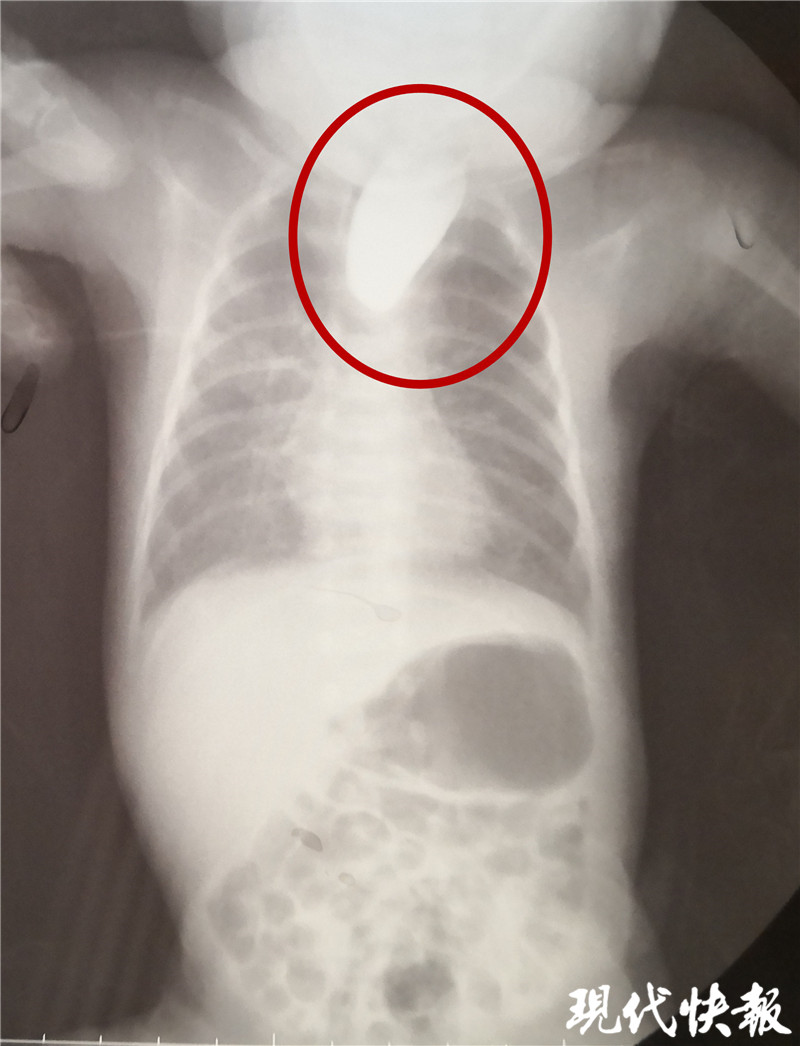

△食道閉鎖

現(xiàn)代快報記者了解到,9月8日,東東從當(dāng)?shù)蒯t(yī)院轉(zhuǎn)入淮安市婦幼保健院治療,檢查顯示東東的食道是個“死胡同”,明確診斷為食道閉鎖。“從片子上看,這個白色的造影劑到了食管上端就無法向下流了,說明孩子的食管上端是不通的、閉塞的。同時,孩子腸腔里面有氣體,這個氣體是通過氣道到食管的遠(yuǎn)端,到達(dá)胃和腸道內(nèi)。”淮安市婦幼保健院小兒外科副主任醫(yī)師夏順林說,這個寶寶如果不及時手術(shù),就會面臨兩個問題,一個就是唾液咽不下去,會嗆入肺部形成吸入性肺炎,同時胃和食管遠(yuǎn)端與氣管相通,胃內(nèi)的胃酸容易反流到氣道里面,進入肺部形成化學(xué)性肺炎。